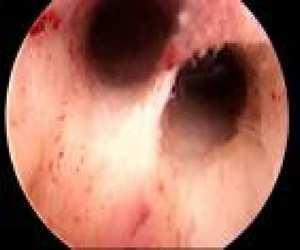

Tubal Patency Evaluation • HSG • HyCoSy • Laparoscopy with chromotubation HyCoSy • Hysterosalpingo Contrast Sonography • In-office sonography • Cavity check for filling defects • Tubal patency assessment • Same timing as SIS or HSG Lesser - Infertility Work-up 65

(SIS or SHG)

Filling Defect Lesser - Infertility Work-up 66

Sonohysterogram

SIS Filling Defect Laparoscopy • Surgical procedure • Diagnose & treat endometriosis • Remove adhesions • Address tubal factor • Remove or reduce septums, fibroids • Not routine Lesser - Infertility Work-up 67